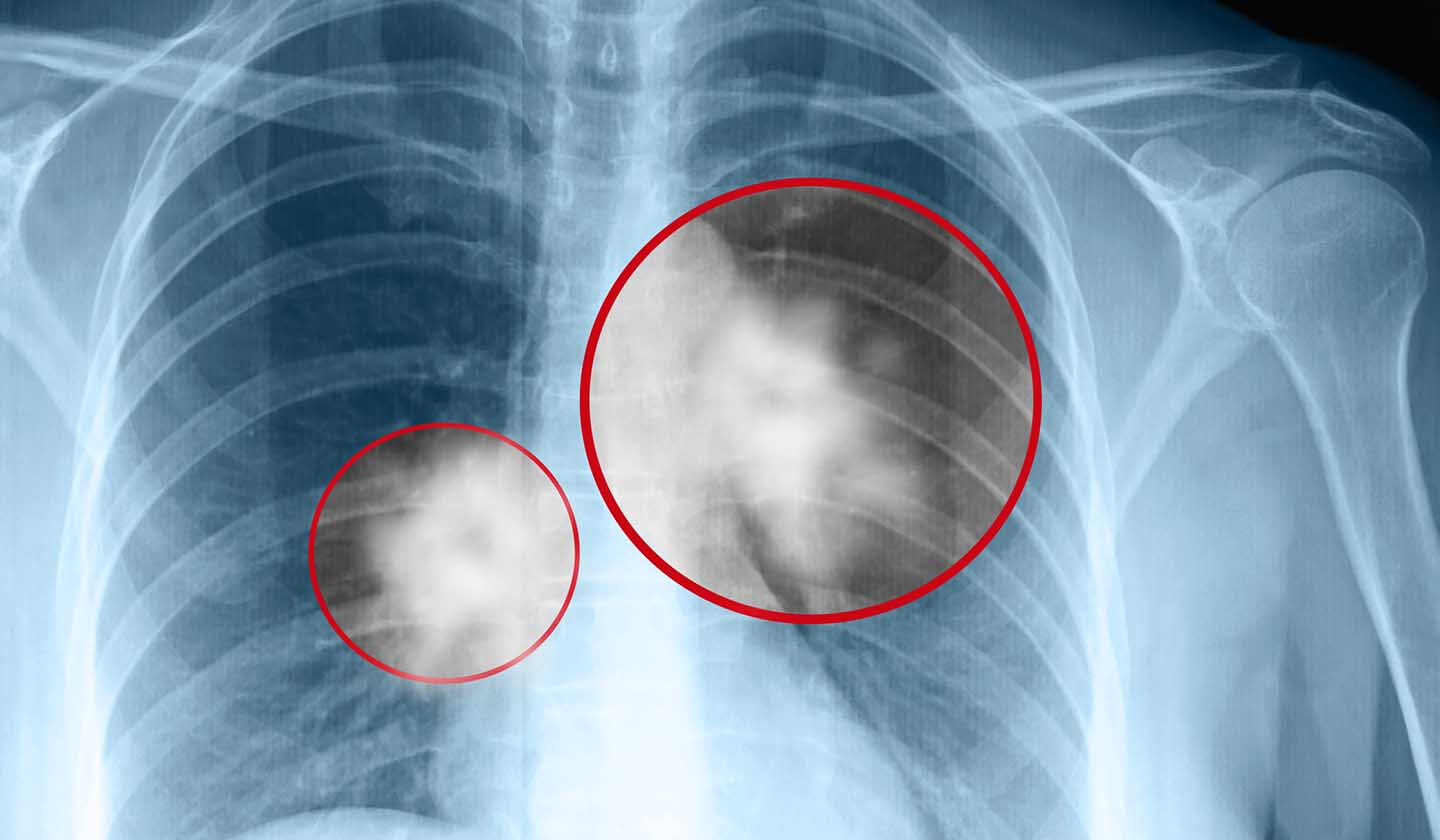

A lista de complicações associadas ao tabagismo é longa e inclui:

• Complicações respiratórias – tosse, asma, DPOC, cancro do pulmão (e outros tumores das vias respiratórias) e infeções respiratórias;

Complicações cardiovasculares e respiratórias